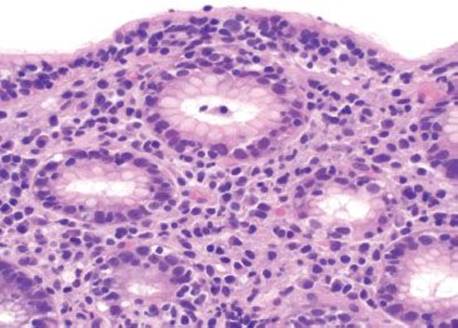

Figure 2.122 Lymphocytic gastritis pattern. There is a prominence of IELs in the surface epithelium, with expansion of the lamina propria by a mixed chronic inflammatory infiltrate that is plasma cell rich. This case had no demonstrable Helicobacter organisms, but additional clinical testing was suggested based on histologic findings.

Figure 2.123 Lymphocytic gastritis pattern (CD3 immunostain). The corresponding CD3 immunostain from the previous case (Fig. 2.122) confirms that the intraepithelial lymphocytes are predominantly CD3+ T-cells. Immunophenotyping the IELs is not required for diagnosis.

Figure 2.124 Lymphocytic gastritis pattern (CD4 immunostain). The corresponding CD4 immunostain highlights a small population of CD4+ T-cells.